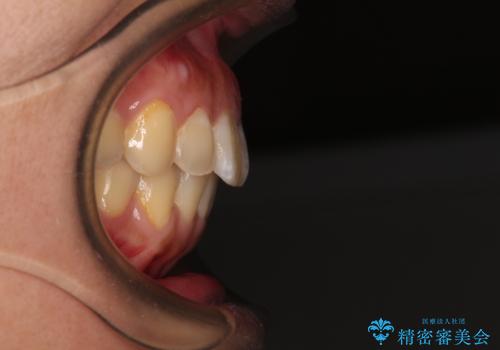

前に出ている前歯を引っ込めたい インビザライン矯正

- 前方に傾斜した上下の前歯を気にして来院された患者様です。

唇の閉じにくさや横顔のシルエットが気になるような突出感ではなかったため、インビザラインを用いて、歯列の遠心移動とIPR(歯と歯の間を削る)により前歯の傾斜を改善していくこととしました。

スムーズに終了すると思われましたが、インビザライン矯正独特の奥歯が咬み合わない状態が続き、更には遠方へ転居されたこともあり、治療期間は長引いてしまいました。